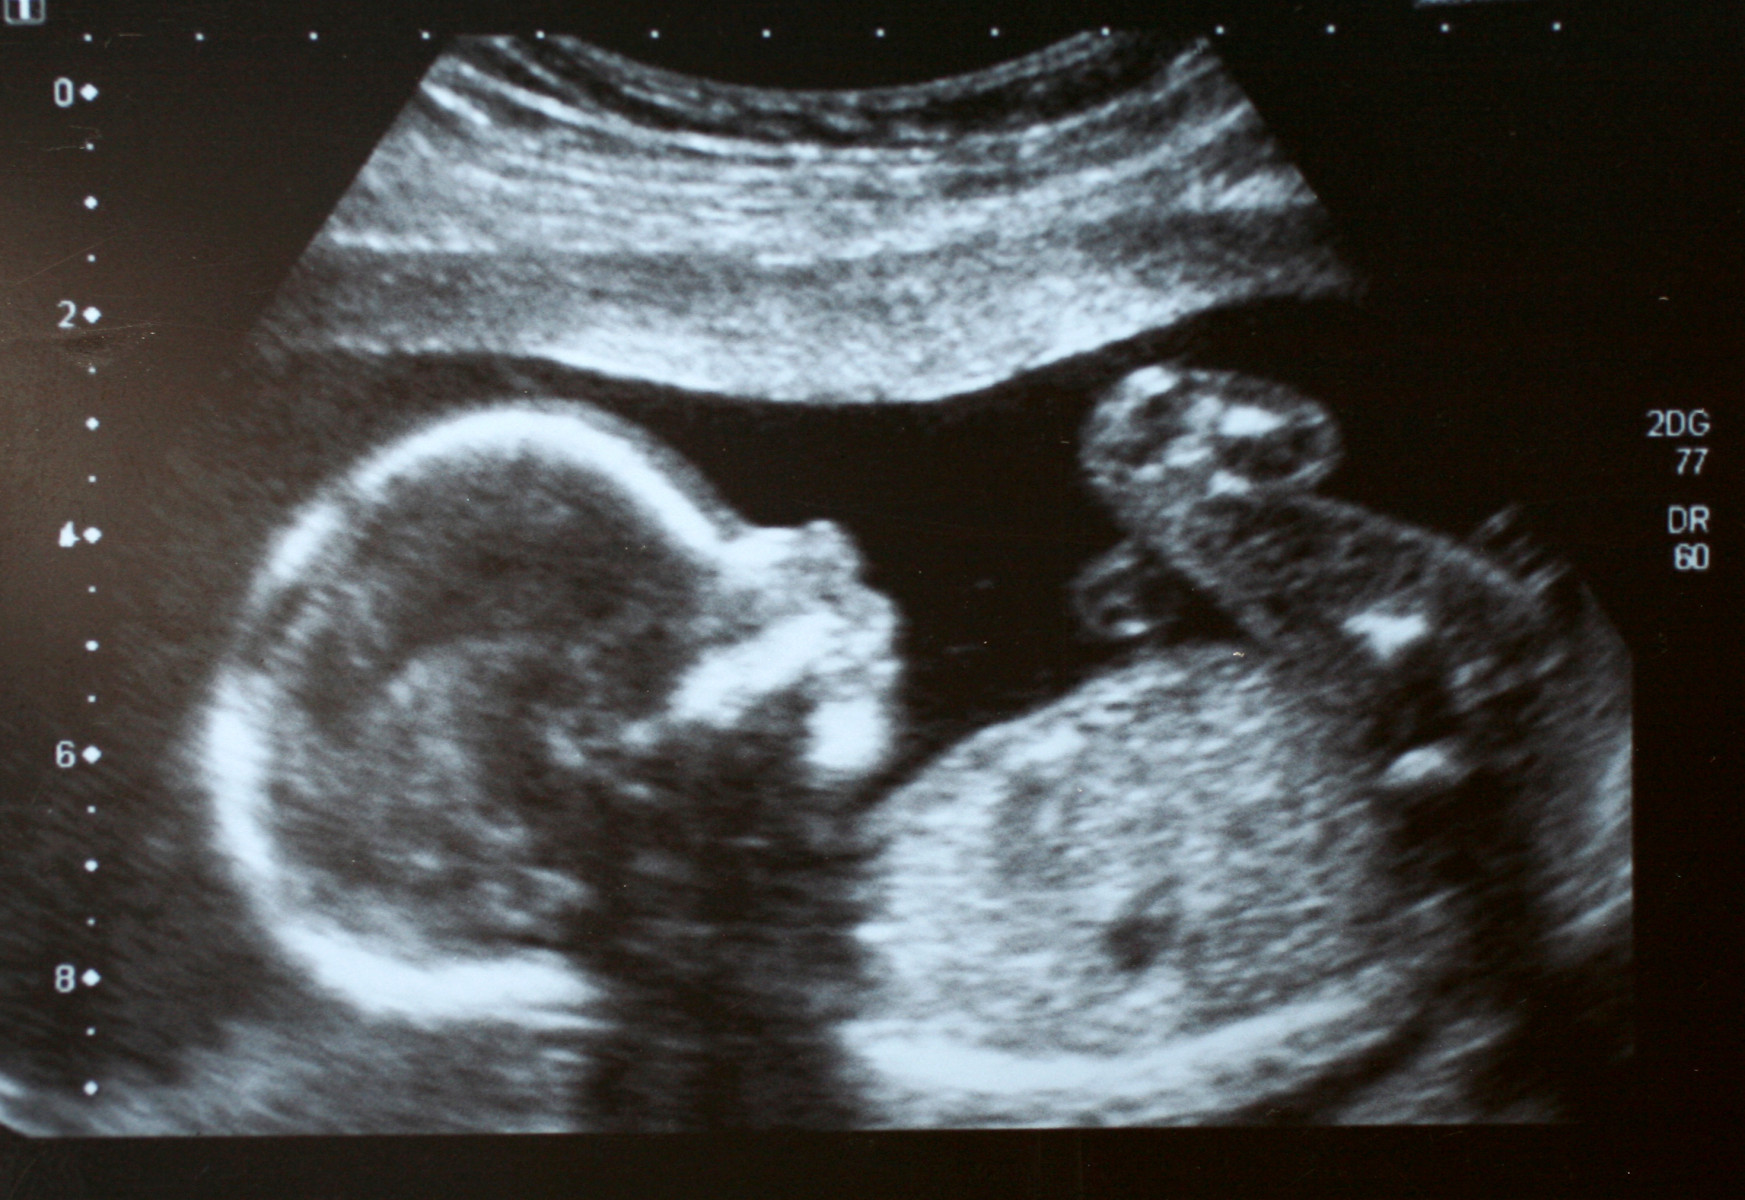

High-risk pregnancy software gets development grant

A new software tool designed by researchers at The Rosalind Franklin Institute,  University of òòò½ÎÑÊÓÆµ and collaborators to support decision making in pregnancies at high-risk of stillbirth is to receive a cash injection.

Around half of stillbirths are associated with fetal growth restriction (FGR), a condition caused by impaired placental function that limits the baby’s growth. Current ultrasound tools detect only around half of FGR cases, and even when identified, there is no treatment. Clinicians must instead make complex decisions about the timing of birth, balancing the risks of premature delivery against the danger of waiting too long.